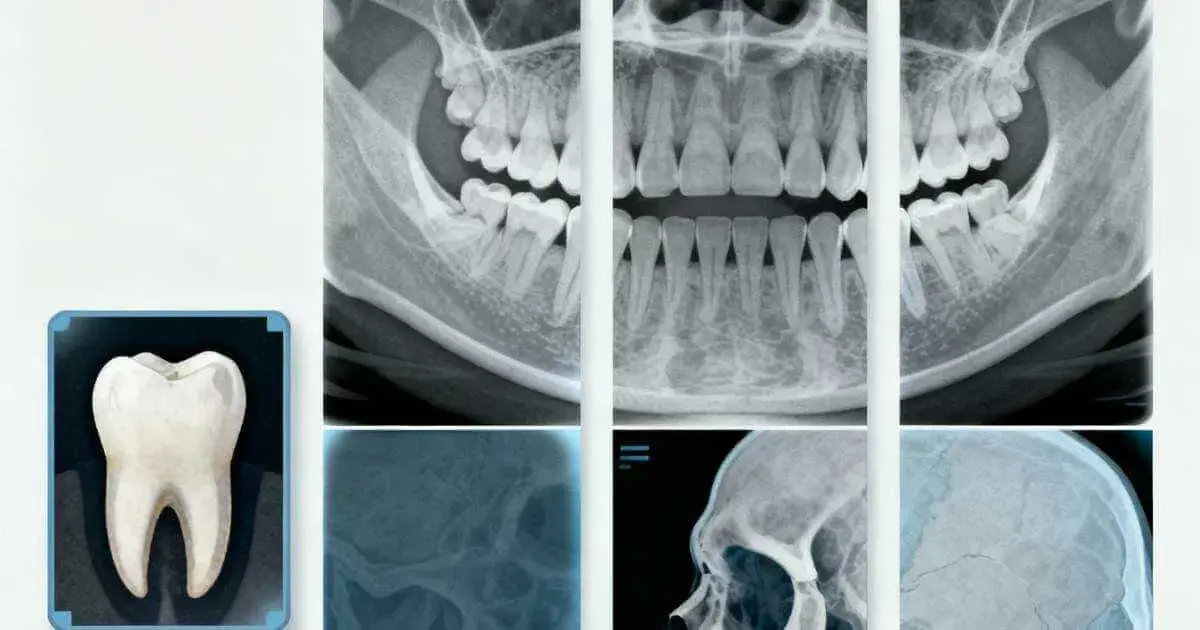

Tipos de radiografías dentales

En odontología, hay varios tipos de radiografías dentales. Cada una se enfoca en aspectos diferentes de la salud bucal. Son clave para hacer diagnósticos precisos y tratamientos efectivos.

Radiografías periapicales

Las radiografías periapicales muestran el diente completo, incluyendo la raíz y el hueso alrededor. Son vitales para evaluar la salud dental. Ayudan a detectar caries profundas y daños en la raíz.

Radiografías interproximales

Las radiografías interproximales son perfectas para encontrar caries entre los dientes. Esta zona es difícil de ver con el ojo. Permiten identificar problemas temprano y actuar rápido.

Radiografías panorámicas

Las radiografías panorámicas muestran toda la boca. Incluyen dientes, mandíbulas y articulaciones temporomandibulares. Son útiles para planificar ortodoncia y ver terceros molares.

Radiografías cefalométricas

Las radiografías cefalométricas se usan en ortodoncia. Muestran el crecimiento y alineación ósea. Son cruciales para planificar y seguir el progreso de tratamientos ortodónticos.